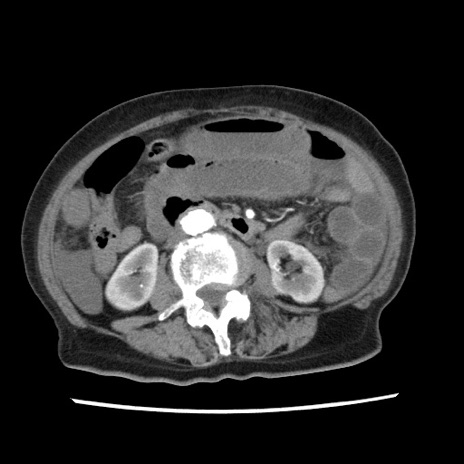

症例1(横断像)

【症例】80歳代女性

【主訴】腹痛

【現病歴】8時間前から腹痛あり来院。

【既往歴】糖尿病、脂質異常症、子宮体癌にて子宮全摘術

【身体所見】意識清明・会話良好だが腹痛で苦悶様、全腹部にわたって反跳痛と圧痛あり

【データ】WBC 13600、CRP 0.14、LDH 224、CK 90